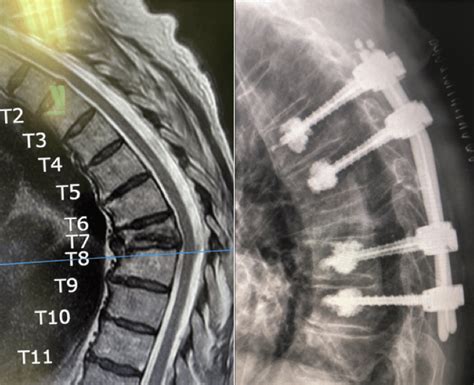

First off, what exactly is a thoracic vertebral fracture ? Simply put, it’s a break in one or more of the vertebrae located in the thoracic region of your spine – that’s the middle part of your back. These fractures can happen for various reasons, such as trauma from a car accident, a fall, or even something as simple as a compression fracture due to osteoporosis. Understanding the different types of thoracic vertebral fractures is crucial for accurate coding. Compression fractures, burst fractures, and fracture-dislocations each have unique characteristics and require specific ICD-10 codes. For instance, a compression fracture typically occurs when the vertebra collapses, often due to osteoporosis or minor trauma. A burst fracture , on the other hand, involves the vertebra shattering in multiple directions, usually from high-impact trauma. Fracture-dislocations are the most severe, involving both a fracture and a displacement of the vertebra, often leading to spinal instability. These different types of fractures not only dictate the ICD-10 code but also influence the treatment approach and expected recovery time. Accurately identifying and documenting the type of fracture is essential for ensuring appropriate medical care and accurate billing.

Moreover, the severity of the fracture plays a significant role in determining the appropriate ICD-10 code . Minor fractures may only require conservative treatment, such as pain management and physical therapy, while more severe fractures might necessitate surgical intervention. The presence of any neurological deficits , such as numbness, tingling, or weakness in the legs, further complicates the coding process and requires additional codes to reflect the patient’s condition accurately. For example, a thoracic vertebral fracture with complete spinal cord injury would be coded differently than a fracture with no neurological involvement. The level of detail in the ICD-10 coding system allows for a precise representation of the patient’s condition, which is vital for both clinical and administrative purposes. This precision ensures that healthcare providers receive appropriate reimbursement for the services they provide and that researchers can accurately track and analyze the incidence and outcomes of thoracic vertebral fractures . Therefore, a thorough understanding of the different types and severities of thoracic vertebral fractures is paramount for accurate and effective coding.

Alright, let’s get down to the nitty-gritty. When it comes to thoracic vertebral fractures , the ICD-10 codes you’ll be looking at generally fall under the S22 category, which covers fractures of the thorax. However, it’s not quite as simple as just picking S22. You’ll need to be more specific to accurately reflect the nature of the fracture. The ICD-10 codes for thoracic vertebral fractures are categorized based on the specific vertebra involved and the type of fracture. For example, a fracture of the T1 vertebra would have a different code than a fracture of the T12 vertebra. Similarly, a compression fracture would be coded differently than a burst fracture or a fracture-dislocation. The level of detail required ensures that the code accurately reflects the patient’s condition and the medical services provided.